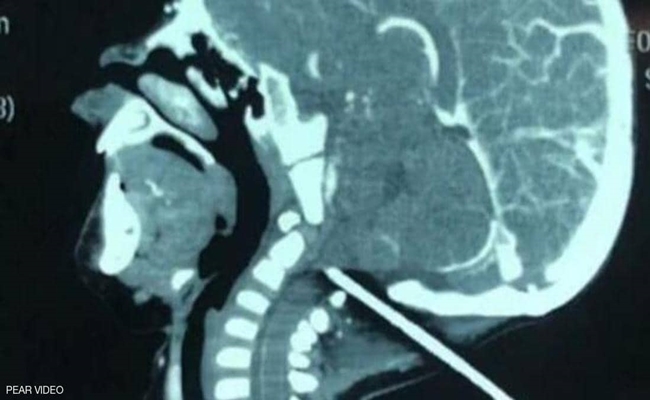

وبعد إخضاع رأس الرضيع للفحص بالأشعة السينية، تبين أن قسما كبيرا من القضيب مستقر في الجمجمة ولا يبعد سوى مليمترات عن الأوعية الدموية في قاع الدماغ.